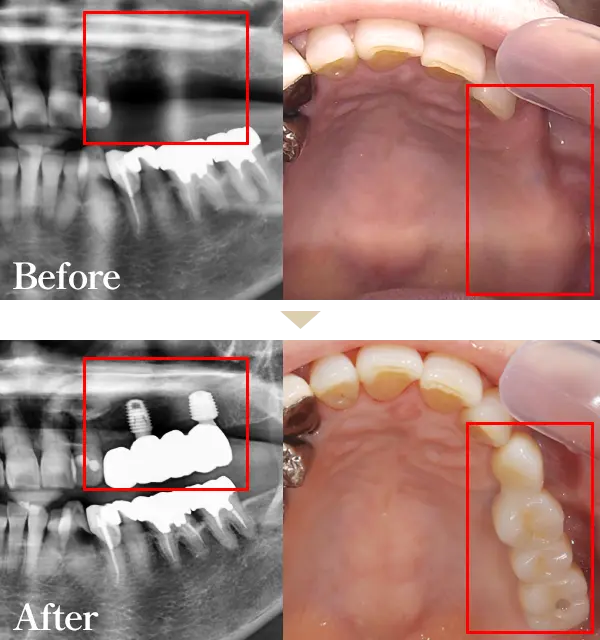

Wデンタルクリニックでは最短2か月で痛みの少ない先進のインプラント治療をご提供することができます。素材は強度にも優れ、身体にも優しい素材になっております。

まるで天然歯のような見た目、噛み応えなどがお勧めポイントです。健康な歯までも削らなくてはいけないブリッジ、違和感が強く噛む力も劣る入れ歯と比べてもメリットが多いのが特徴です。